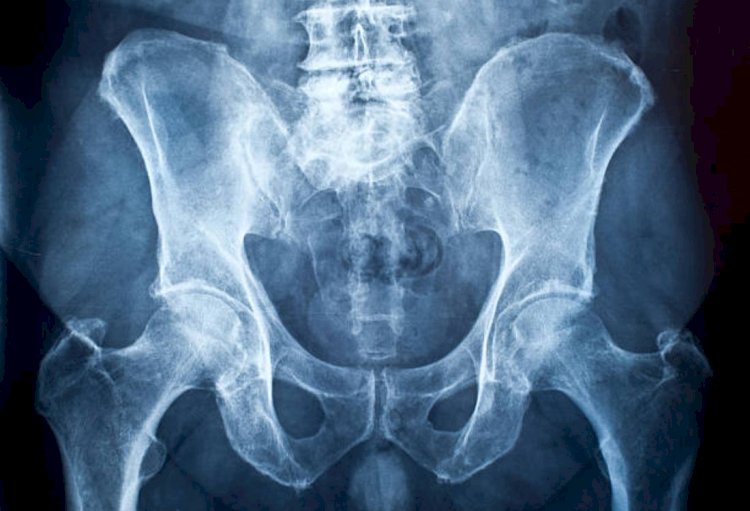

जांच के बाद डॉक्टर्स भी उसे देखकर हैरान रह गए। उन्होंने ऑपरेशन कर युवक के गुदा से केन को बाहर निकाल।

डॉक्टर्स ने कहा कि पहले बिना ऑपरेशन के युवक की गुप्तांग से केन निकालने के प्रयास किए गए, लेकिन केन गुप्तांग द्वार के भीतर होने के कारण उसका ऑपरेशन करना पड़ा।